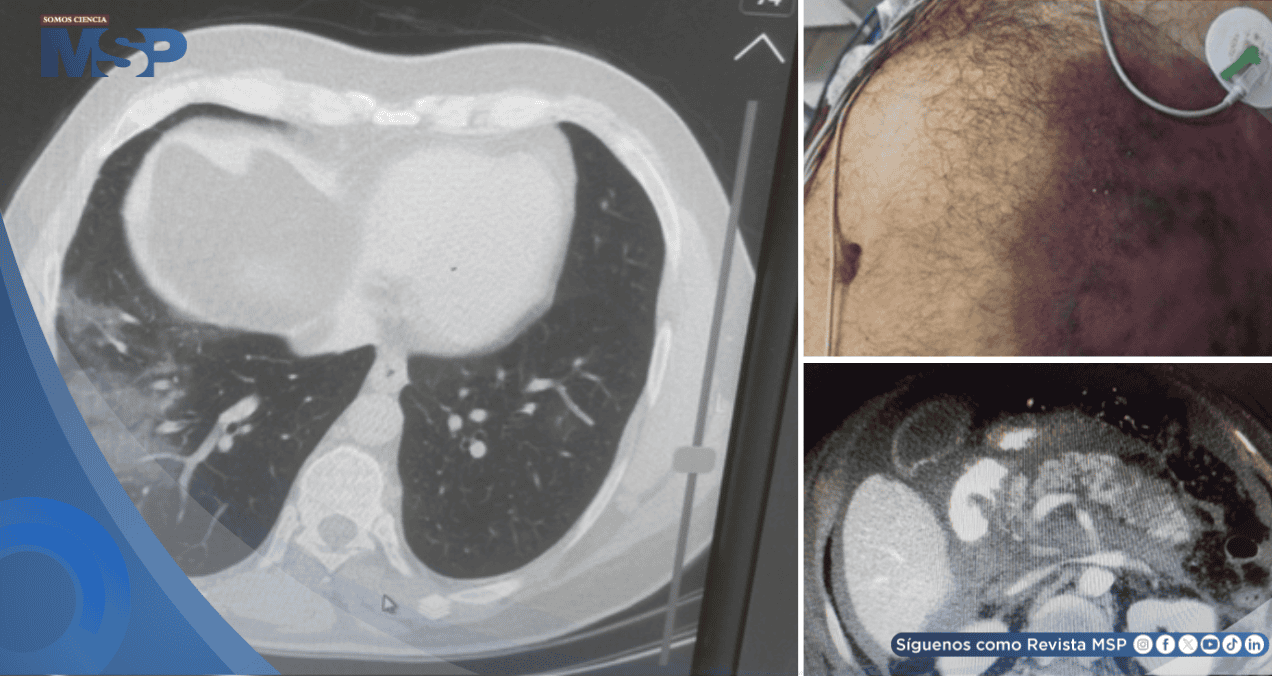

En el abdomen se observaba distensión, dolor generalizado a la palpación y un área de equimosis (moretón) en el flanco izquierdo, conocido como signo de Grey Turner, que sugiere hemorragia retroperitoneal.

Las imágenes revelaron una pancreatitis necrosante aguda severa, con más del 30% del tejido pancreático afectado por necrosis y acumulación de líquido inflamatorio en los espacios circundantes.

La tomografía computarizada es fundamental no solo para el diagnóstico, sino también para estadificar la enfermedad; las imágenes de este paciente mostraron el grado más severo, con múltiples colecciones de líquido.